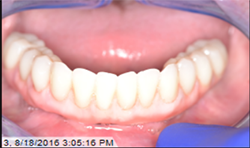

After normal healing and integration, 5 x 5 mm healing abutments with 2.5 mm wells were placed. At the impression appointment, the sulcus was prepared using a sulcus reamer and a PVS impression was taken and sent to the lab. The patient was happy with the wax try-in and the lab was instructed to finish the case. Delivery was uneventful (Figs. 5, 6).

At the one-month, post-op appointment the patient reported being able to eat corn on the cob and was happy with the fit and function of his hybrid, and the prosthesis continued to perform properly at subsequent follow-up visits.

At a second appointment, four Bicon SHORT implants, three 4 x 6 mm and one 3.5 x 8 mm were placed in the mandibular arch (Figs. 9, 10). After normal healing time, both the maxillary and mandibular arches were fitted with a fixed hybrid prosthesis fabricated from a TRINIA substructure and Ceramage denture teeth. The patient was happy with the fit, function and comfort (Fig. 11).